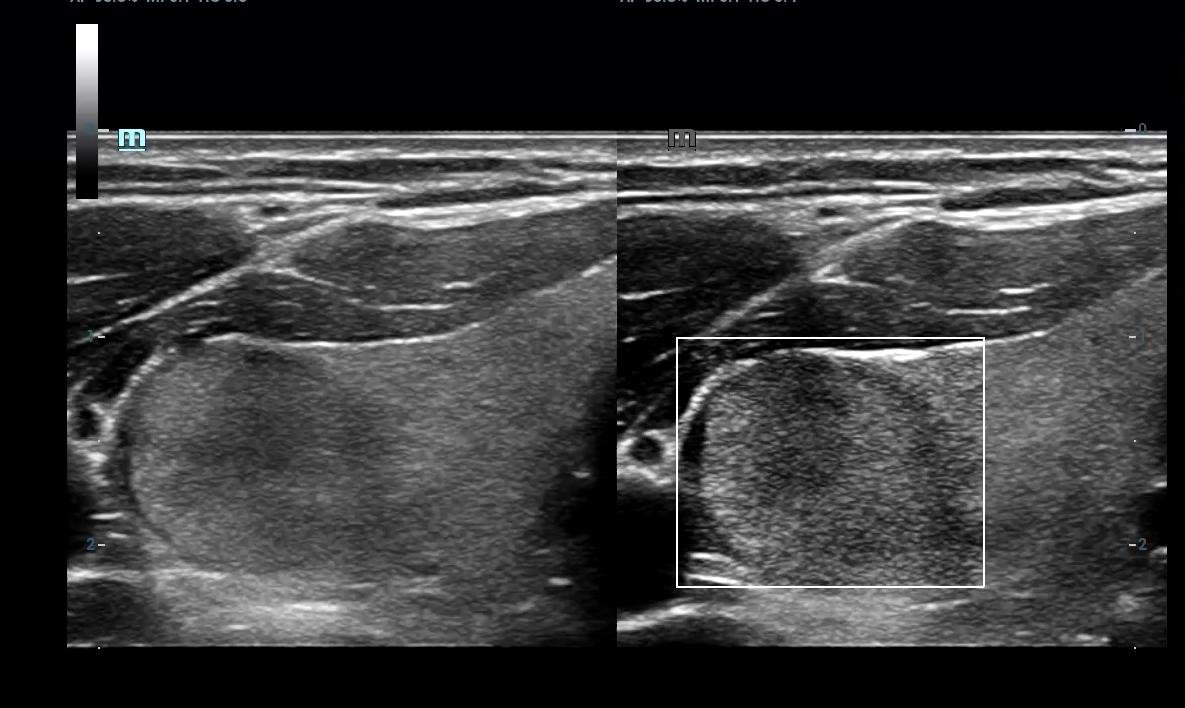

• High End SHEAR WAVE ELASTOGRAPHY For LIVER FIBROSIS/THYROID MALIGNANCY/BREAST CANCER

Liver Elastography